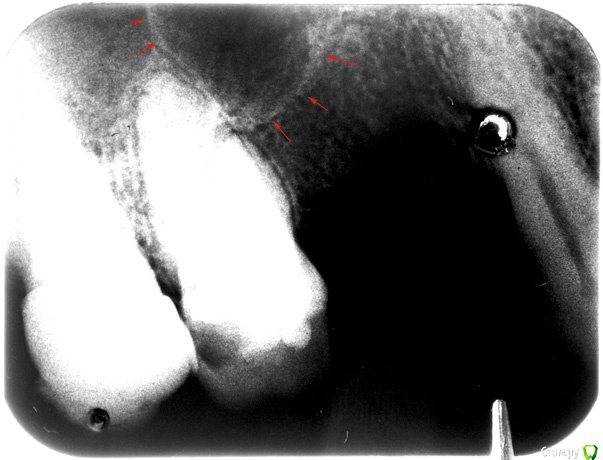

red_butler Опубликовано 13 февраля, 2017 Поделиться Опубликовано 13 февраля, 2017 Хм... А что видите и что тогда посоветуете? Rg является дополнительным способом диагностики. Если дистанцироваться от Ваших жалоб, то на снимке осложненный кариес, а именно хронический апикальный периодонтит. Диагноз киста можно поставить проведя гистологическое исследование. И если мне не мерещится, то в области первого премоляра есть фрагмент корня.Шестой зуб, если степень его разрушения позволяет провести реставрацию, нужно лечить у эндодонтиста. 1 Ссылка на комментарий

Анбо Опубликовано 15 февраля, 2017 Автор Поделиться Опубликовано 15 февраля, 2017 (изменено) ОПТГ нет. Сходил к другому врачу. Сказала, что снимок плохой (темный), но тоже увидела кариес корня и кисту. Вряд ли они сговорились. Но они зато видели снимок «живьем». Может плохой снимок + потеря качества при перефотографировании привели к тому, что на приведенном здесь фото что-то теряется? Вот поиграл светом-тенью – может что-то проявилось? Это не то, что стрелочками обозначил? Но она была не столь категорична по поводу удаления («Лучше удалить, но можно пока оставить. Но все равно через некоторое время все вернется»). И сказала, что если зуб вскрывать, то будет еще хуже. Мне сделали разрез, чтобы выпустить гной, и назначили азитромицин. Прокомментируйте, пожалуйста.Если на снимке не все видно, укажите, пожалуйста, какие части наиболее важны, я могу в фотошопе сделать их наиболее контрастными. Гистологическое исследование, о котором писал red_butler, не везде делают? Оно имеет какое-нибудь более конкретное название? Изменено 15 февраля, 2017 пользователем Анбо Ссылка на комментарий

Гарриевич Опубликовано 15 февраля, 2017 Поделиться Опубликовано 15 февраля, 2017 это дно верхнечелюстной пазухи"кисты" не видать 5 Ссылка на комментарий

DmitrySH Опубликовано 16 февраля, 2017 Поделиться Опубликовано 16 февраля, 2017 Если у Вас еще сохранились сомнения, то сделайте КТ , все будет понятно. Никакой кисты, просто бухта гайморовой пазухи. 1 Ссылка на комментарий

Bier Опубликовано 16 февраля, 2017 Поделиться Опубликовано 16 февраля, 2017 там четко есть гранулема на медиальном корне. Может ее и назвали "кистой"?? 2 Ссылка на комментарий